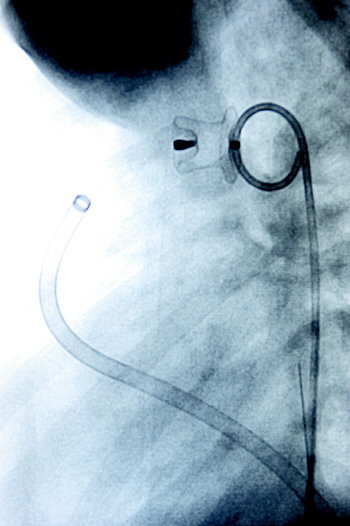

▲专家们在介入手术室借助世界上最先进的DSA血管造影机设备,为普片小朋友做心脏动脉导管未闭封堵术

▲封堵器精确地放到心脏动脉缺损处